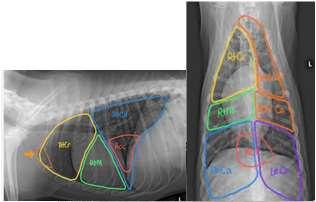

Diagnosis:thoracicradiographs;skinbiopsies –apoptotickeratinocyteswithlymphocyte satelitosis;ruleoutinfections,ectoparasites (Cheyletiella)